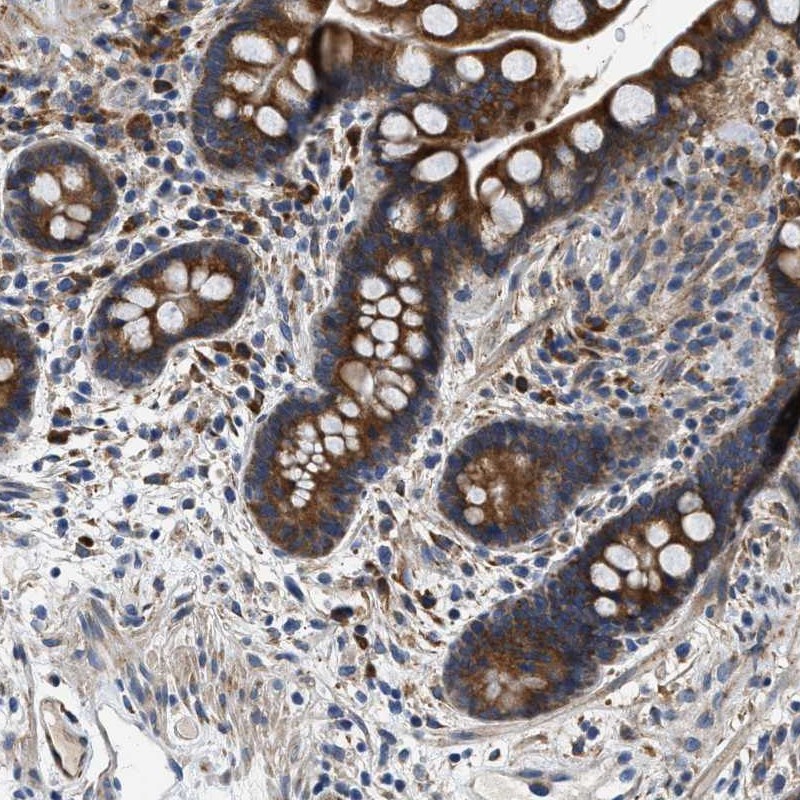

Immunohistochemical staining of human colon shows strong cytoplasmic positivity in glandular cells.